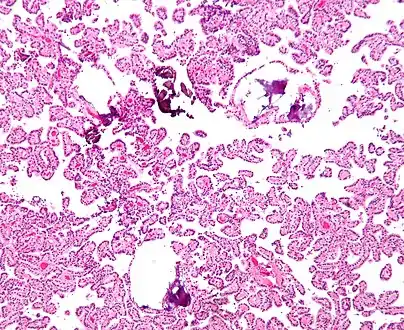

Micrograph of a choroid plexus papilloma. H&E stain.

The tumor is neuroectodermal in origin and similar in structure to a normal choroid plexus. They may be created by epithelial cells of the choroid plexus.